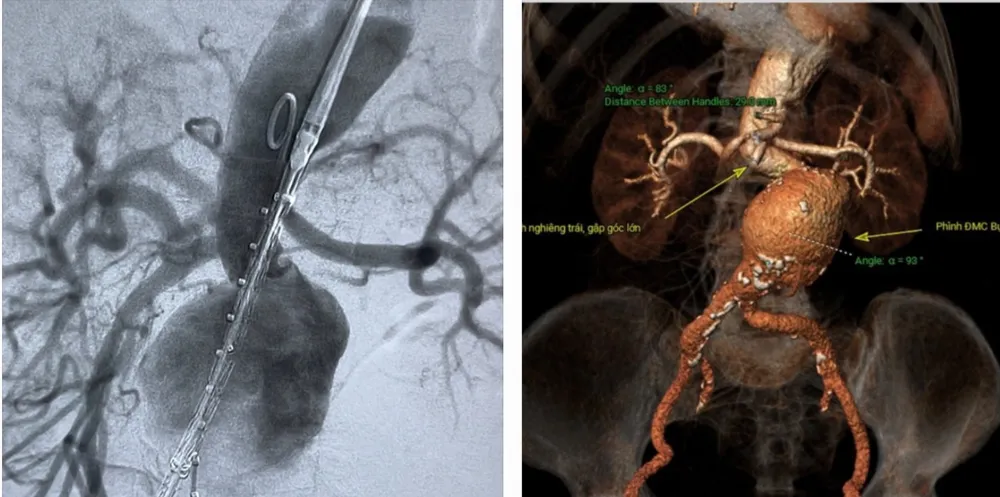

Chiều 17-2, tại bệnh viện Trung ương Huế, sức khỏe bà Nguyễn Thị M. (79 tuổi, trú Cam Lộ, Quảng Trị) dần ổn định sau khi được các bác sĩ can thiệp đặt stentgraft cấp cứu thành công.

Các bác sĩ cứu sống bệnh nhân Nguyễn Thị M. tại Trung tâm tim mạch – Bệnh viện Trung ương Huế |

Bệnh nhân Nguyễn Thị M. có tiền sử tăng huyết áp, vào viện sáng 16-2 trong tình trạng đau bụng dữ dội, trụy tim mạch kèm khối phình lớn ở bụng, đập theo nhịp tim, tiên lượng nguy kịch nếu không xử trí kịp thời.

Qua thăm khám và xử trí cấp cứu ban đầu, các bác sĩ chẩn đoán bệnh nhân bị sốc do túi phình lớn động mạch chủ bụng dọa vỡ, nguy cơ vỡ cao. Sau đó, bệnh nhân được siêu âm bụng và chụp CT xác định túi phình rất lớn, động mạch chủ bụng dọa vỡ.

Các bác sĩ cấp cứu tim mạch can thiệp và hồi sức tim mạch của Bệnh viện Trung ương Huế đã phối hợp xử trí cấp cứu ổn định tình trạng huyết động. Ngay lập tức, tối cùng ngày, bệnh nhân được chuyển tới trung tâm can thiệp tim mạch để tiến hành can thiệp cấp cứu thành công đặt stentraft động mạch chủ bụng bít hoàn toàn túi phình lớn động mạch chủ bụng.

Giáo sư Phạm Như Hiệp, Giám đốc Bệnh viện trung ương Huế cho biết, việc phối hợp và cấp cứu kịp thời các trường hợp bệnh tim mạch phức tạp và nguy kịch là công tác quan trọng và hoàn chỉnh của một trung tâm tim mạch hoàn chỉnh. Bệnh lý động mạch chủ là rất phức tạp và nguy cơ tử vong rất lớn, để cứu chữa được kip thời không chỉ đảm bảo cả về vật tư trang thiết bị y tế thiết yếu như stentgraft mà còn phải có đầy đủ cả ekip can thiệp và hồi sức tim mạch giỏi.